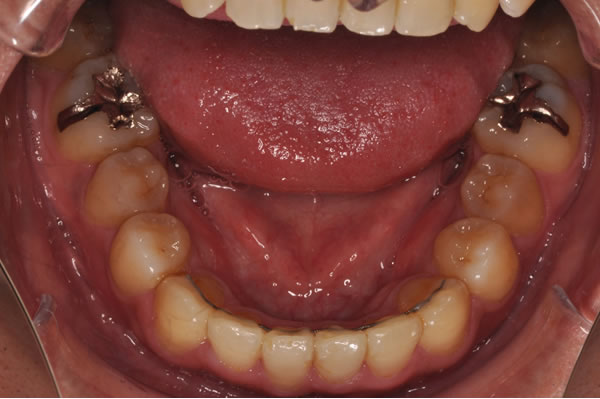

反対咬合症例

治療前(初診)